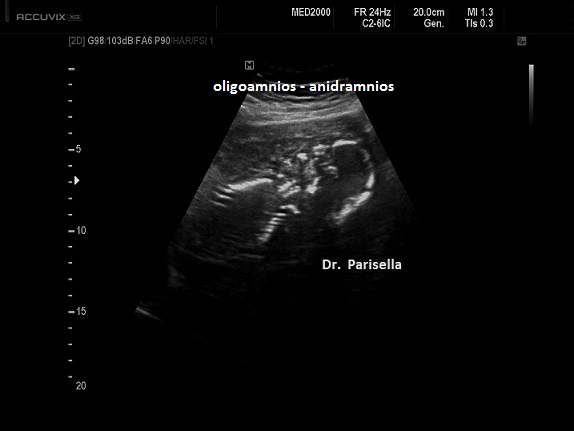

Possono essere presenti: idrope, cardioaptie congenite, labiopalatoschisi, oligoamnios, anomalie genito-urinarie, anomalie gastro-intestinali, anomalie del SNC.